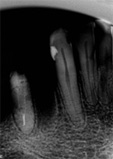

antes depois